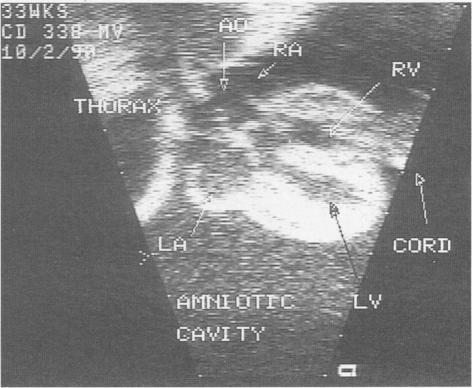

心脏超声检查在结构性异常和心律失常中的应用。识别与治疗。

Cardiac ultrasonography in structural abnormalities and arrhythmias. Recognition and treatment.

Fetal cardiac ultrasonography has become an important tool in the evaluation of fetuses at risk for cardiac anomalies. It can both guide prenatal treatment and assist the management and timing of delivery. We recommend that a fetal echocardiogram be done when there is a family history of congenital heart disease; maternal disease that may affect the fetus; a history of maternal drug use, either therapeutic or illegal; evidence of other fetal abnormalities; or evidence of fetal hydrops. The optimal timing of evaluation is 18 to 22 weeks' gestation. An entire range of structural cardiac defects can be visualized prenatally, including atrioventricular septal defect, ventricular septal defect, cardiomyopathy, ventricular outlet obstruction, and complex cardiac defects. The outcome for a fetus with a recognized abnormality is unfavourable, with less than 50% surviving the neonatal period. Fetal cardiac arrhythmias are also a common occurrence, 15% in the series described here. Premature atrial or ventricular contractions are most commonly seen and usually require no treatment. Supraventricular tachycardia can result in hydrops and require in utero treatment to prevent fetal demise. Complete heart block, particularly in association with structural heart disease, has a poor prognosis for fetal survival.

胎儿心脏超声检查已成为评估有心脏异常风险胎儿的重要工具。它既可以指导产前治疗,又有助于分娩的管理和时机选择。我们建议,当存在先天性心脏病家族史、可能影响胎儿的母体疾病、母体有治疗性或非法药物使用史、其他胎儿异常证据或胎儿水肿证据时,应进行胎儿超声心动图检查。最佳评估时机是妊娠18至22周。产前可以看到一系列结构性心脏缺陷,包括房室间隔缺损、室间隔缺损、心肌病、心室流出道梗阻和复杂心脏缺陷。已确诊异常的胎儿预后不佳,新生儿期存活率不到50%。胎儿心律失常也很常见,在此系列研究中占15%。最常见的是房性或室性早搏,通常无需治疗。室上性心动过速可导致水肿,需要宫内治疗以防止胎儿死亡。完全性心脏传导阻滞,尤其是与结构性心脏病相关时,胎儿存活预后不良。